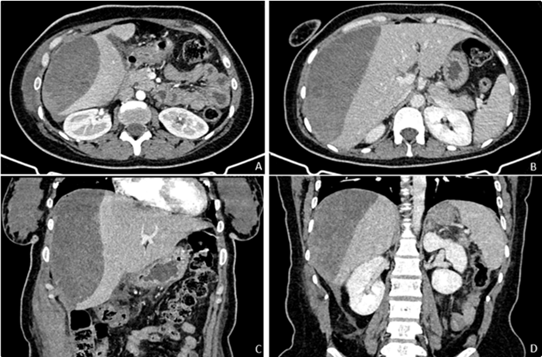

Figure

1: Pre-operative CT scan showing an acute pancreatis. No angioma, tumor or

vascular malformation were apparent

(A)

Arterial phase axial maximum intensity projection; (B) Arterial phase coronal

maximum intensity projection; (C) Portal venous phase axial maximum intensity

projection ; (D) Portal venous phase coronal maximum intensity projection